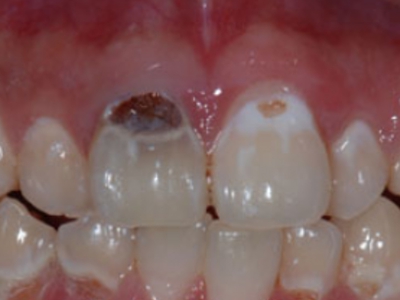

酸蚀症牙齿缺损不平整图

酸蚀症患者的牙齿会发生缺损,轻度时仅表现为牙齿尖端凹凸不平,有少量骨质缺失,缺损处有黄褐色至红褐色斑点,该病可能是长期接触外源性酸性物质而致病。